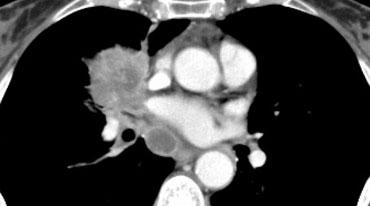

Hình minh họa

M1c1: Nhiều tổn thương di căn ngoài lồng ngực trong một cơ quan đơn lẻ.

Hầu hết các cơ quan đều có thể bị ảnh hưởng trong bệnh di căn.

Di căn thường gặp ở tuyến thượng thận, hạch bạch huyết, não, xương và gan.

M1c2: Nhiều tổn thương di căn ngoài lồng ngực trong nhiều hệ cơ quan.